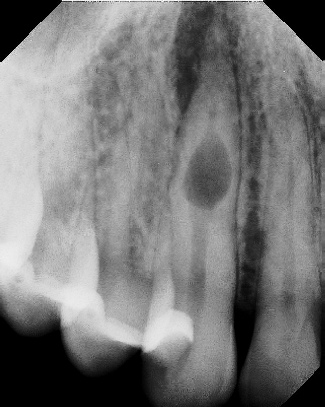

COMPLICATED ANATOMY LARGE LESIONS CALCIFIED CANALS PERFORATION / RESORPTION SEPARATED INSTRUMENTS SURGICAL CASES RETREATMENT / pOST REMOVAL OPEN APICES ACCESS THRU CROWNS Root Canal Case Portfolio

6 mos.